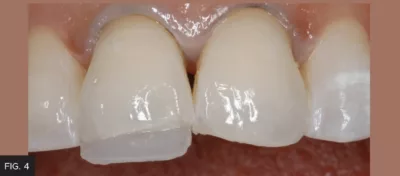

A layer of Evanesce Enamel White (ENW) was placed into the lingual matrix in the area corresponding to tooth #8, using a Compo-Ject™ (Clinician’s Choice) composite gun. To avoid trapping air, the tip of the compule never left the composite. A Multi-Use Composite Instrument (Cosmedent®, Inc.) was used to adapt a very thin, uniform layer of ENW between the inciso-buccal line angle and the scribed line on the lingual matrix. The lingual matrix was placed on the teeth and this layer was gently connected to the lingual margin of the preparation using the Multi-Use Instrument. A #3 Composite Brush (Cosmedent, Inc.) lightly coated with ResinBlend LV (Clinician’s Choice) smoothed and further thinned out the lingual shelf, removing any excess ENW at the inciso-facial line angle with the Multi-Use Instrument. This unfilled modeling resin does not contain HEMA, so it will not alter the physical properties of the composite, nor will it discolor over time. The lingual layer was then light-cured for 20 seconds and the lingual matrix was gently removed. (FIG. 4)

lingual shelf using Evanesce ENW

The lingual shelf is made using Evanesce ENW and replaces the more translucent lingual and incisal enamel. A very thin layer of ENW is first placed in the lingual matrix, then connected to the preparation once the lingual matrix is replaced onto the teeth, then light-cured for 20 seconds.